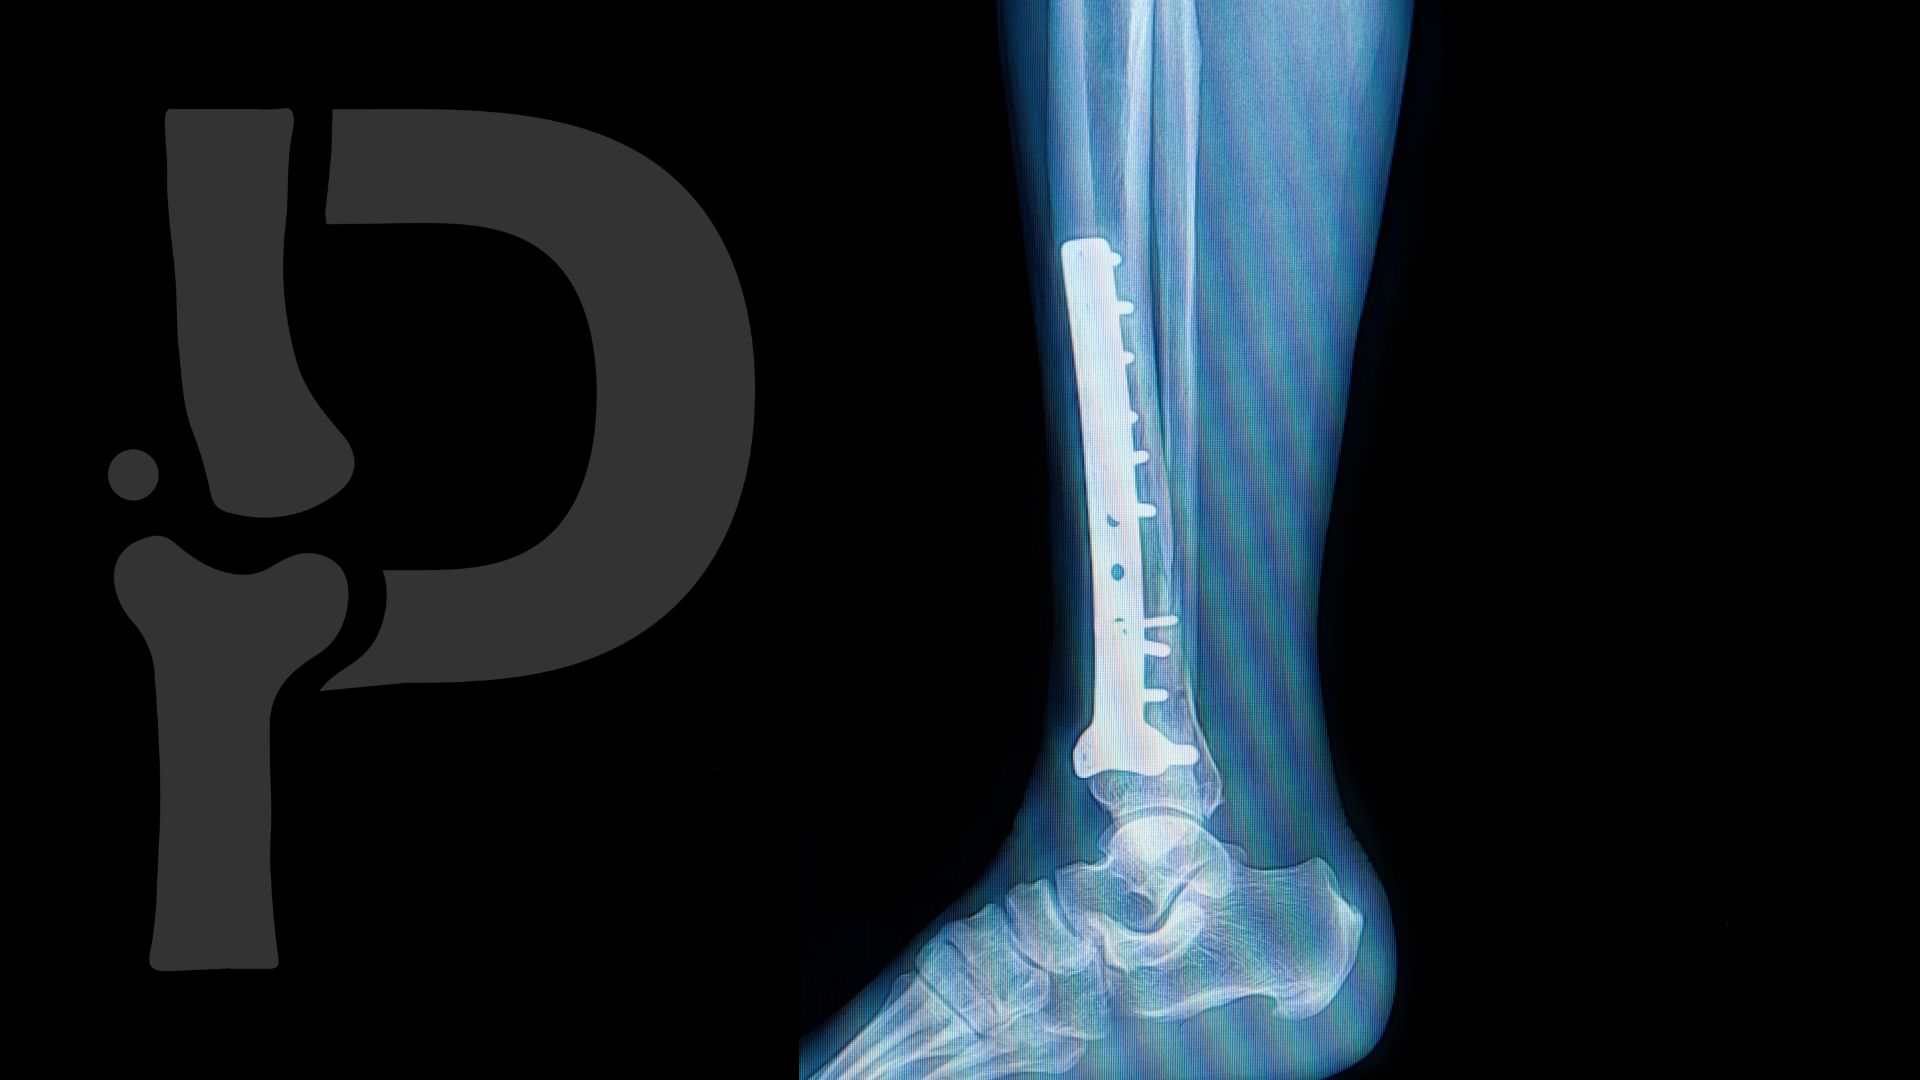

Tratamiento: El tratamiento de las fracturas de tobillo puede variar según la gravedad de la lesión, pero generalmente implica la inmovilización del tobillo con una bota o un yeso para permitir que los huesos sanen correctamente. En algunos casos, puede ser necesario un procedimiento quirúrgico para realinear y fijar los fragmentos fracturados con placas, tornillos o alambres.